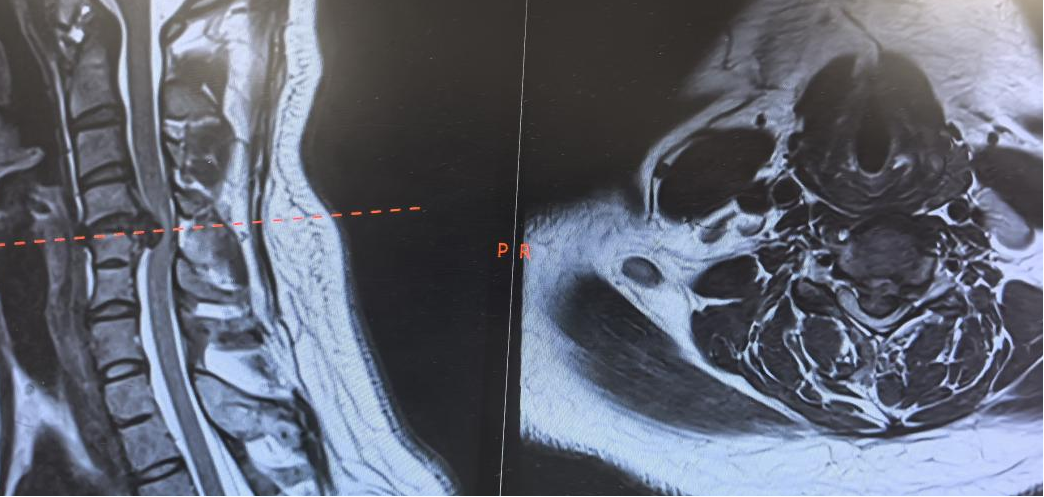

“能像正常人一样拧开矿泉水瓶盖啦!我以前想都不敢想!”术后病房里,29岁的渭南姑娘小王(化名)握着恢复力气的左手,眼含热泪对自己的主管医生、西安市红会医院脊柱病院颈椎病区汤立波医生说。谁能想到,就在几天前,她还因颈椎里一颗“巨型炸弹”——占据椎管容积约80%空间的罕见巨大的颈椎间盘突出,面临着随时可能瘫痪的绝境。 小王的困境要从四年前说起。最初的四肢麻木没引起重视,可两年前症状突然加重,她和家人跑遍各大医院,却都因手术风险太高被婉拒,只能靠保守治疗勉强维持。随着时间推移,她的病情不断恶化:走路不稳、左手肌力严重下降,连最基本的拧瓶盖动作都做不到,更可怕的是她还存在颈椎先天发育畸形——颅底凹陷、寰枕融合、颈5、6椎体分节不全,再加上偏胖体型和常年低头工作的习惯,让颈椎间盘突出愈发严重,椎管被挤压得只剩不到20%空间,连走路都像踩在棉花上,稍不注意就会摔倒,哪怕是急刹车这样的外力,都可能让她瞬间瘫痪。 “不做手术,瘫痪是迟早的事;做手术,一半概率成功,一半概率直接瘫在手术台上。”当小王一家慕名找到西安市红会医院脊柱病院颈椎病区副主任医师王彪医生时,这样残酷的现实摆在了所有人面前。王彪结合病史及检查结果,颈椎间盘突出症诊断明确,且脱出髓核占到椎管的80%以上,属于巨大型椎间盘脱出,颈部脊髓严重受压。这是近几年临床比较少见的一例高风险颈椎手术,术中稍有不慎,就可能出现脊髓损伤导致瘫痪。巨大的风险让很多医院的医生望而却步。看着年轻姑娘眼中的绝望,想到她若失去行动能力的未来,医生的职责让王彪绝不推诿。术前谈话时,小王的父母紧紧攥着王彪医生的手,语气坚定:“医生,孩子就交给您了,我们相信您!”这份沉甸甸的信任,成了医护团队迎难而上的动力。 为了减少创伤,让年轻的患者更好恢复,王彪和团队放弃了“后路间接减压+前路手术”的常规方案,决定一步到位——采用颈椎前路间盘切除椎管减压植骨融合内固定术,通过精准微创的前路手术直接取出突出椎间盘。这意味着手术操作要在极度狭窄的空间里进行,对术者技术提出了很高的要求。手术操作如同在“拆炸弹”,每一个动作都要精准到毫米。手术台上,紧张的气氛几乎凝固。一个半小时里,手术室里只有器械轻微的碰撞声,每一秒都在与风险赛跑。最终在不损伤神经的情况下,全部取出了压迫神经的巨大脱出髓核组织。 术中髓核组织 “手术成功!”此时,等候在手术室外的家属瞬间红了眼眶。术后令人惊喜的是,小王的四肢麻木感逐渐消失,左手肌力恢复如常——她不仅没瘫痪,还重新拥有了正常人的生活!“术前只求不瘫就好,没想到能恢复得这么好,这就是重生啊!”小王和父母握着王彪的手,感激的话语哽咽在喉。 王彪医生介绍,患者小王的病情因先天发育问题叠加常低头的不良生活习惯导致。患者年龄小且椎间盘突出巨大,这在临床非常少见,手术风险确实超出常规。作为医生“为患者搏希望”是责任。而这份医者担当,与家属的信任相互支撑,最终成就了这场跨越风险的生命奇迹。如今,小王已顺利康复,她的故事也成了医患同心、共克病魔的温暖注脚。 王彪 西安市红会医院脊柱病院颈椎病区副主任医师,博士,硕士研究生导师,陕西省科技新星,西安市红会医院高层次人才,中华医学会脊柱微创外科学组青年委员,西安市青年联合会委员,陕西省中西医结合学会骨质疏松疾病委员会常务委员,中国老年医学会脊柱微创委员,中国医药教育协会骨质健康分会委员,SCI杂志编委。发表论文70篇(SCI 49篇,中文21篇)。获陕西省科技进步一等奖、二等奖各1项,获得国家发明、实用新型等专利共31项,其中美国发明专利1项,国家发明专利6项。主刀完成世界首例MAZOR X辅助上颈椎强直性脊柱炎伴齿状突骨折的寰枢椎椎弓根螺钉复位后弓切除减压矫形手术、世界首例新型骨水泥桥接螺钉系统联合经皮椎体成形术治疗狭窄型SCOVF、西北首例2D机器人辅助椎间孔镜手术。完成脊柱各类手术近6000余例。术前颈椎MR